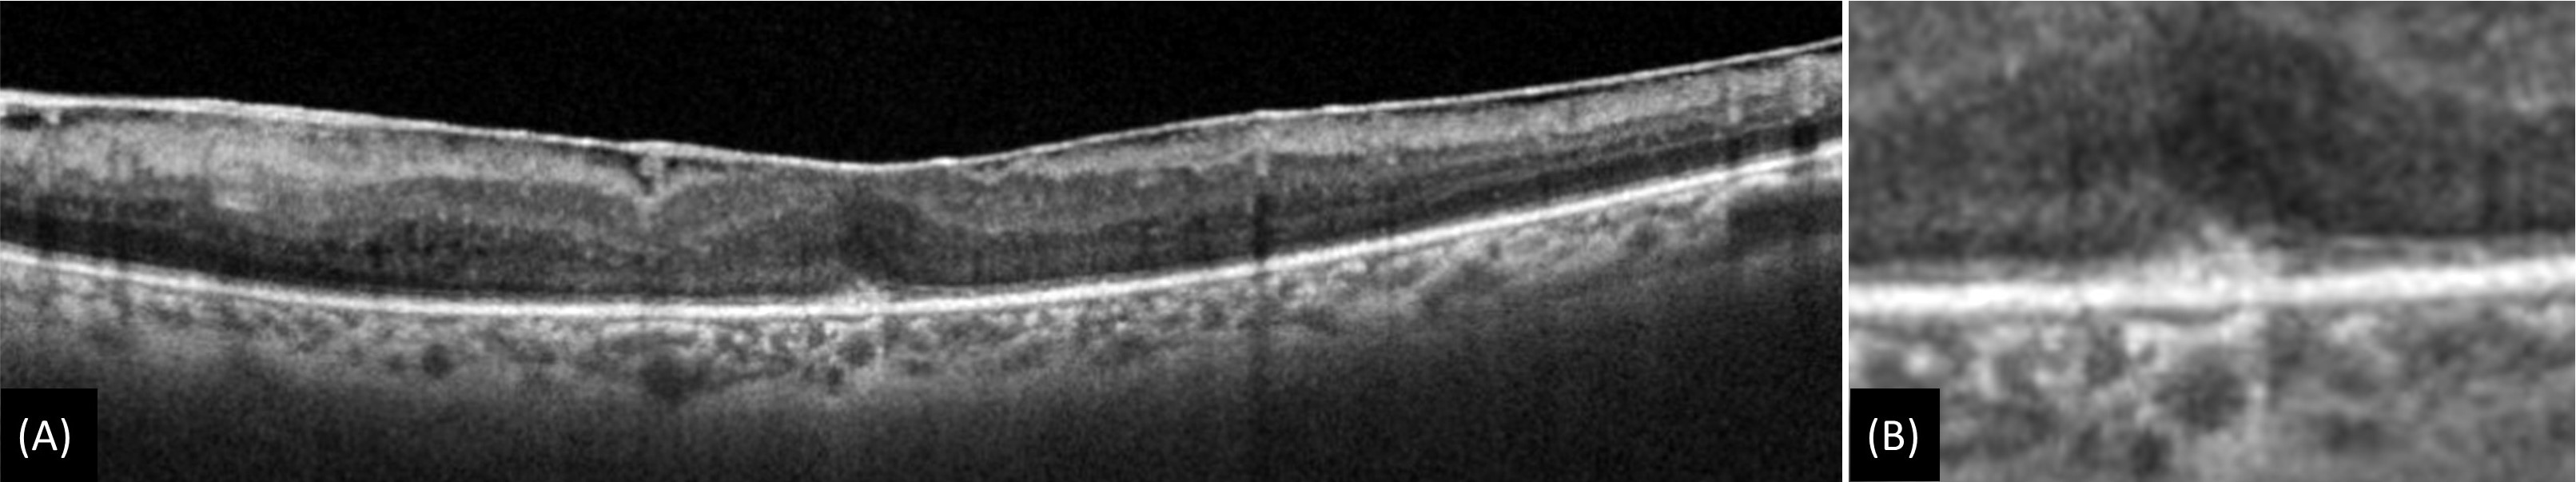

Figure 3: (A) Epiretinal membrane with cotton ball sign which is characterized by small, fuzzy subfoveal hyperreflective area between the inner segment ellipsoid zone (EZ) and the interdigitation zone (IZ). (B) Magnified image